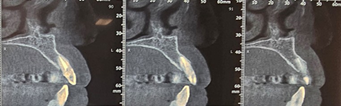

Radiological examination (Figure 2) showed no periapical infection or desmodontal enlargement, and the presence of a thin layer of vestibular bone, so tooth 22 was deemed irrecoverable.

Figure 2. Sagittal sections of the CBCT of the patient